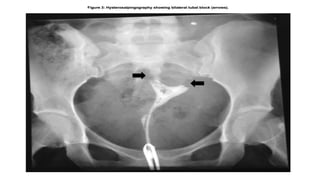

Hysterosalpingraphy

Tubal findings Endometrial findings

• Occlusion

• Hydrosaplinx

• Beading

• Tobacco pouch

• Maltese cross appearance

• calcification

• Synechiae

• Irregular contour

In known cases or in circumstances in

which genital TB is highly suspected,

HSG should be avoided because of

risk of activation.